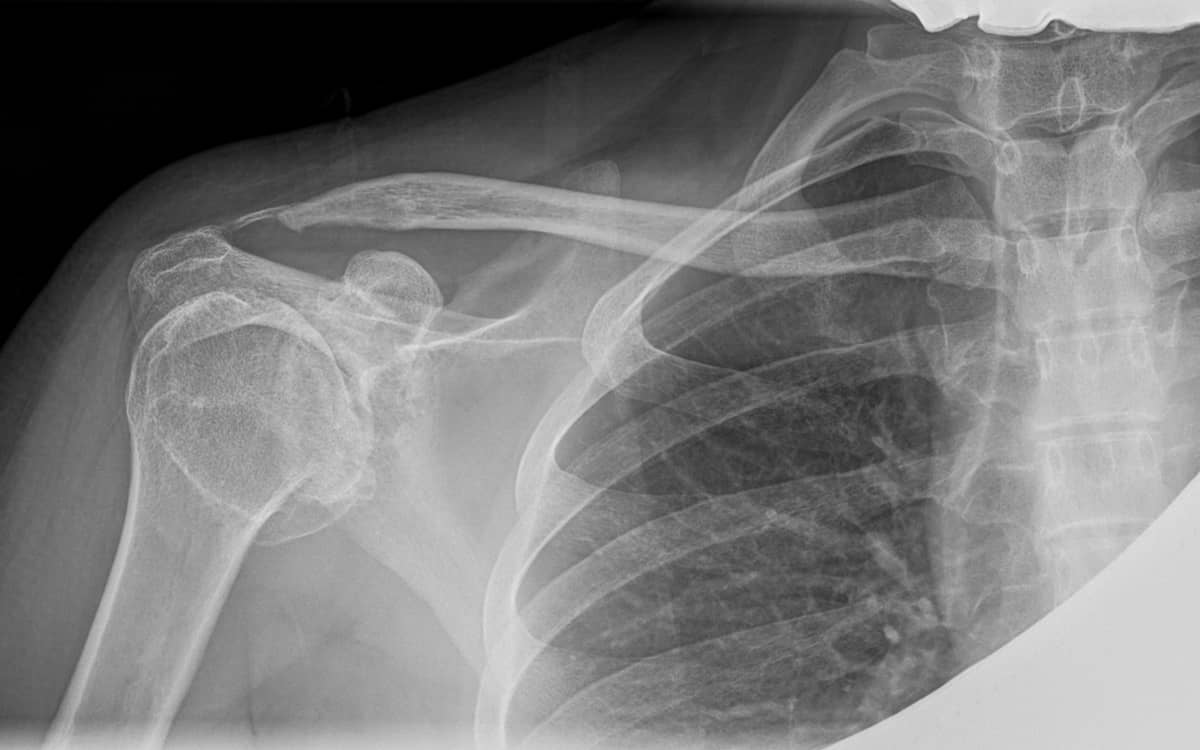

Shoulder pain can be due to soft tissue injuries (commonly the rotator cuff or the biceps tendon), wearing away of the articular cartilage at the head of the glenoid or the humerus (or glenohumeral joint, at the ball and socket of the shoulder), or at the acromial clavicular (AC) joint, where the collarbone meets the shoulder scapula. But unlike problems with the knee or ankle cartilage, wear in the shoulder has been nearly impossible to solve.

The shoulder’s AC joint is also quite different. It is comprised of angular surfaces, confined to a tight space. When arthritic, the joint forms spurs (osteophytes) that dig into the underlying rotator cuff. This causes pain when the shoulder is elevated or during weight lifting. Many long-term weight lifters develop AC joint arthritis.

Surgery for arthritis at the glenohumeral joint is problematic, as cartilage repair procedures have not worked reliably. Surgery to remove spurs and inflammatory tissue often helps for a while but is not curative. At the AC joint, removing the spurs and partially opening the joint—while maintaining its structural support—is one of the strategies for buying time. Full resection of the joint leads to later pain and instability.